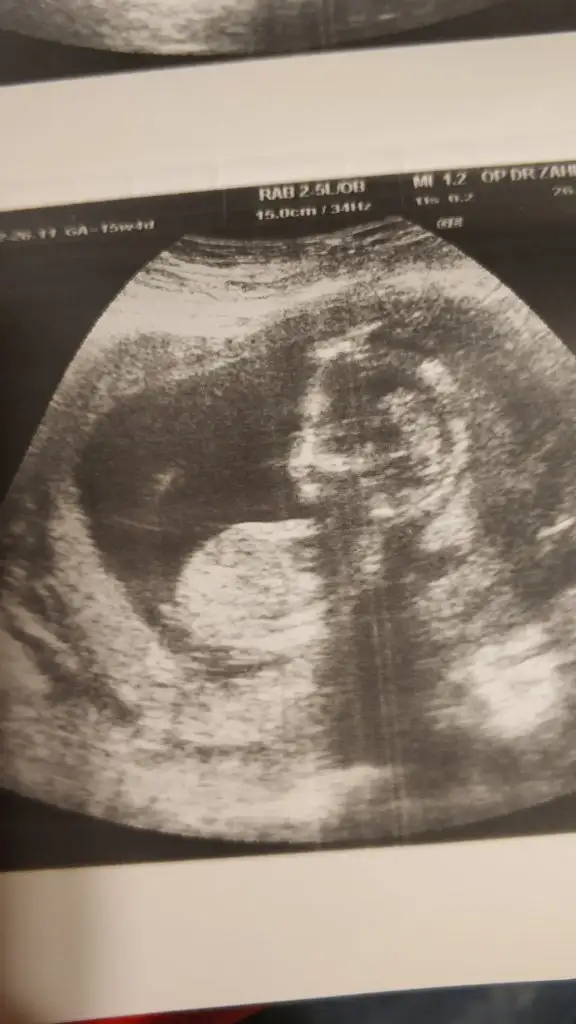

M mely15 bi bakarmısın canım ben tahmin ettim arkadaşa sen ne diyorsun 12+4 usgKızlar kızlarvideodan ekran görüntüsü aldığım 2 fotoğrafta nub birinde paralel birinde dik duruyor hareket ettiği sırada değişiyor olabilir mi

bilemedim sizede ekleyim istedim yakaladığım kısımları ❤ M mely15

Ikra meyra Eki Görüntüle 2601535 Eki Görüntüle 2601536

Kız gibiIkra meyra tekrar usg paylaşın demiştiniz sat a göre 12+1 ultrasona göre 12+6 çıktık ❤Pazartesi tekrar gideceğim ama bunu da atmak istedim belki bir tahmin olur

11 12 13 haftalar nub için uygun şimdilik sanki erkek gibi gibi dediğimiz usgleri paylaşırmısınızIkra meyra bir bakarmısın canım

Malesef bir tek bu var 11+5 olarak başka yok11 12 13 haftalar nub için uygun şimdilik sanki erkek gibi gibi dediğimiz usgleri paylaşırmısınız